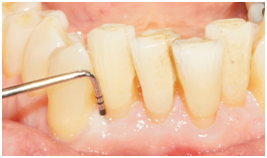

A 72 year-old white male was referred due to an isolated increasing probing depth on the disto-facial aspect of the mandibular right lateral incisor which had an initial PD of 10 mm with BOP (Table 2). Increase in probing depth is illustrated in the clinical photo (Figure 6). The patient was seen for a comprehensive periodontal examination and a periodontal maintenance visit after scaling and root planing was previously performed. His oral hygiene and plaque control was very good and no local factors were detected at that time. Radiographic evaluation revealed a slight radiolucency on the distal of tooth #26 (Figure 7).

Figure 6 Pretreatment clinical photo of tooth #26 with distal facial PD of 10mm.

Supportive periodontal therapy was performed on a regular basis starting 6 weeks after surgery and every three months making sure not to instrument the surgical site subgingivally. The patient’s plaque control was optimal. The patient was recalled 6 months after surgery. Full mouth periodontal charting was completed. The disto-facial surface of tooth #26 exhibited a remarkable reduction in PD and BOP (Table 2). The patient was pleased with the esthetics and function. 12 months follow up was performed that revealed stable periodontal readings when they were compared with the 6 months readings. At the 12 month reevaluation, the PD was 3mm at the disto-facial surface of #26. There was a CAL gain of 6 mm (Figure 9) (Figure 10). Table 2 present clinical measurements at baseline, 6 and 12 months and documents a tendency for continued improvement in PD and CAL from baseline.

Figure 9 Probing 12 months after surgery reveals PD of 3 mm on the disto-facial aspect of tooth #26.